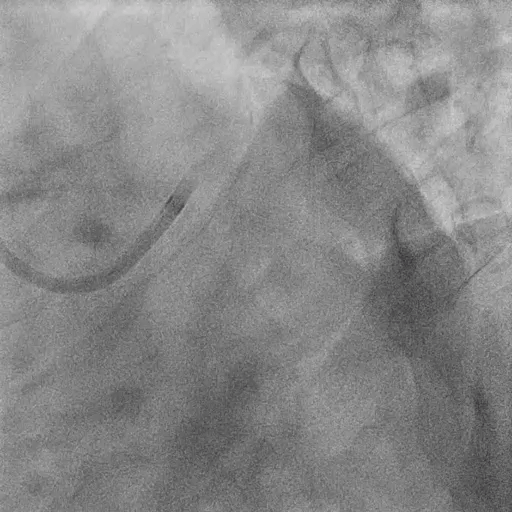

Procedure

Pre-LM-LAD PCI:

FFR at LAD: positive (0.60)

IVUS findings:

Distal landing zone: EEM diameter 4.2 mm, plaque burden 35%

Ostial LAD: plaque burden 72%, MLA 2.9 mm²

Proximal landing zone: EEM diameter 5.2 mm, plaque burden 30%, fibrolipidic plaque morphology